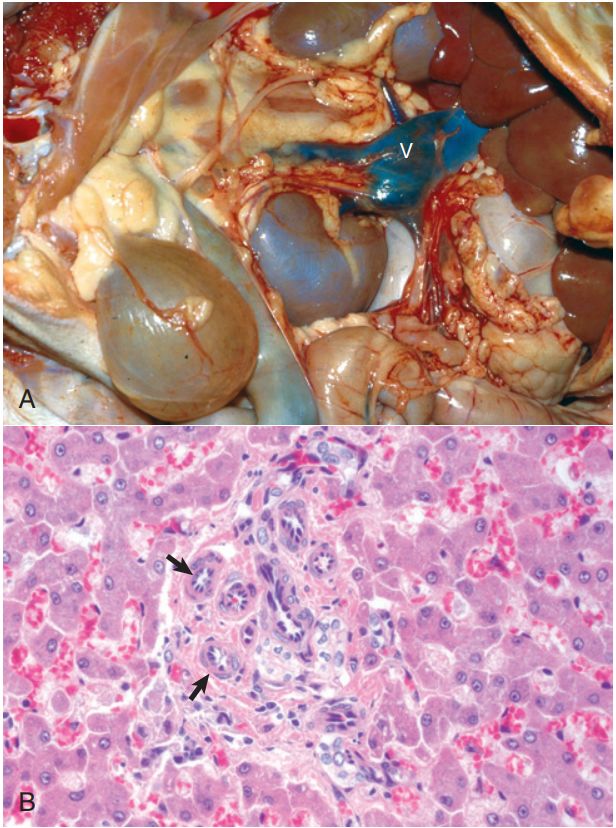

68.有關犬先天性門脈體循環分流 (congenital portosystemic shunt) 的敘述何者正確 ?①患犬容易因肝腦病(hepatic

encephalopathy)產生昏迷 ②肝臟因嚴重纖維化呈灰白及萎縮狀 ③組織病變的特徵是門脈區小動脈增生

(B)僅①③